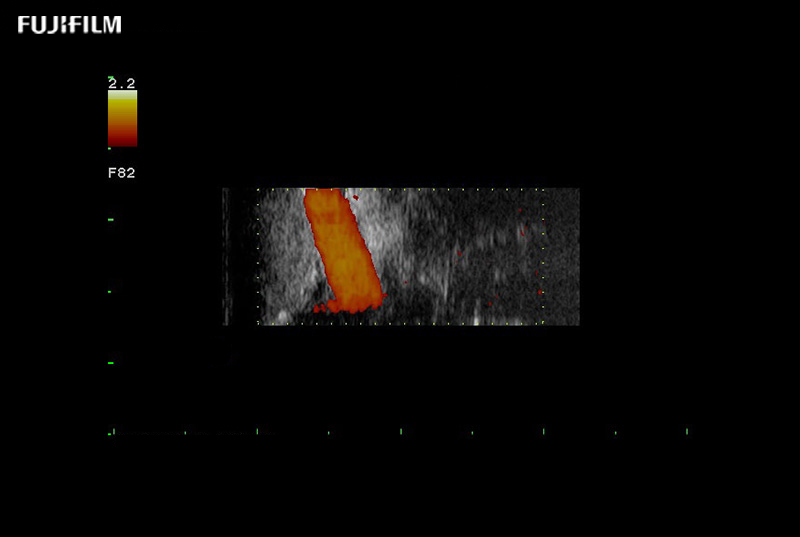

Extraordinary high-resolution digital imaging

Multi-Parametric imaging modalities